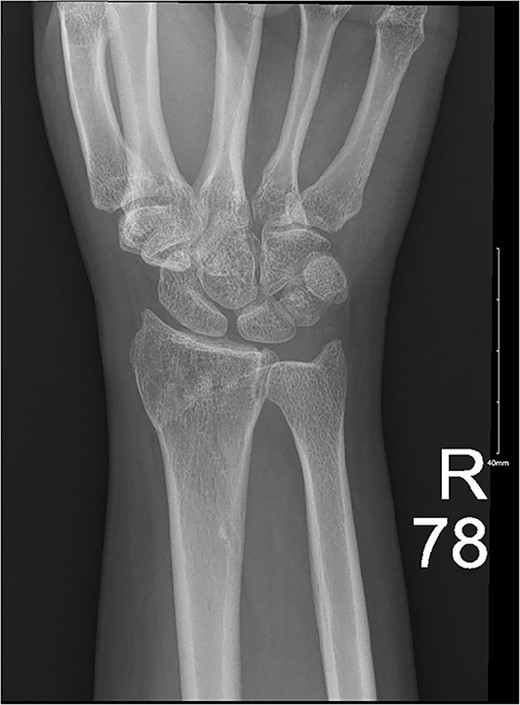

A 29-year-old female presented to the emergency department with pain and deformity of her right wrist as well as a laceration of her right thumb following an MVA with airbag deployment as an unrestrained passenger. The incident happened when another vehicle crashed sideways into the driver’s side while moving at ~50 kmph. There was limited ROM at the MCP joint due to pain. Imaging showed an oblique fracture at the base of first metacarpal bone medially (Fig. 3), so the patient was admitted for wound exploration and repair of other concomitant injuries. The wound was irrigated, the neurovasculature and tendons were observed to be intact, the laceration was sutured, and thumb spica was applied. Subsequent clinic visits showed a hyperpigmented scar as well as a decreased ROM in her wrist and fingers as the radius was still going through the healing process (Fig. 4).

Ongoing healing is seen in the distal radius fracture. The fracture line is barely visible.